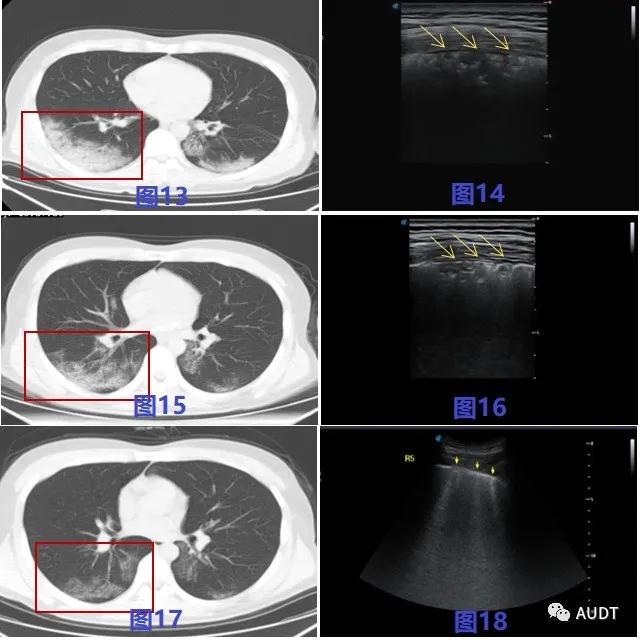

同一患者肺部病灶进展与转归超声图像变化表现 :图13-14 为进展期,图15-17为转归期 CT扫描显示双肺大片样,条带样实变影较图13 逐步明显吸收,图16较图14 超声显示病变肺组织缩小,实变组织内气体强回声增多,图18 在图16表现的基础上肺部病灶大部消失,可见少量B线残留。